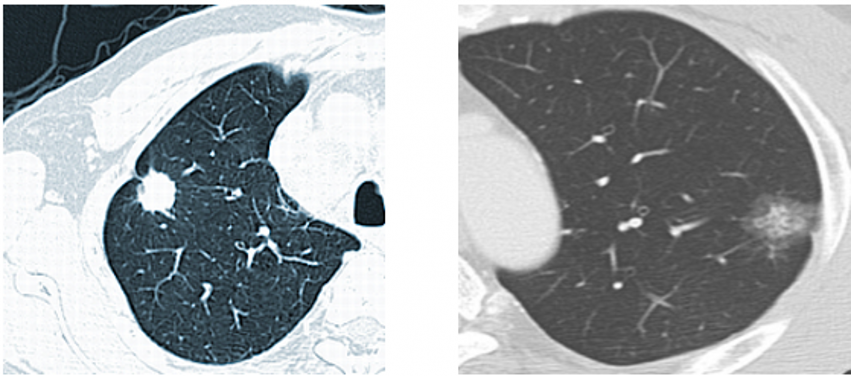

另外一个患者治疗后,随访3个月结节完全消失。